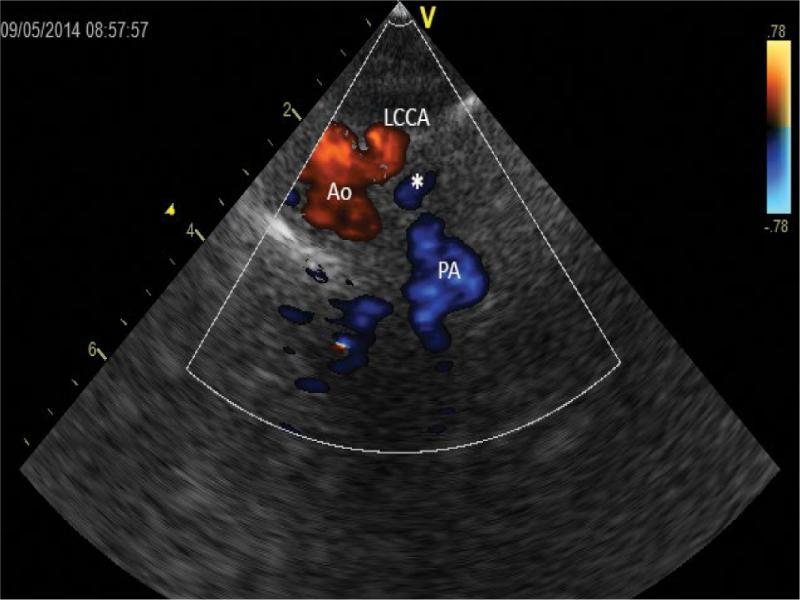

A further shift of ultrasonic beam upwards, systole. Cross-sections of the ascending aorta (Ao) and the left common carotid artery (LCCA), which runs separately at the same level – both vessels are coded in red – as well as the ductus arteriosus (*) and the pulmonary trunk (PA) – these vessels are filled with blue color, indicative of a flow in the opposite direction

Echocardiographic diagnosis revealed situs solitus, compatible venoatrial and atrioventricular junctions; aortic dextroposition (40–50%) over a large (approx. 12 mm) perimembranous ventricular septal defect (VSD). There was a bidirectional ventricular septal defect shunt, with left-to-right predominance. Right-sided aortic arch. Due to difficult anatomical conditions, no conclusion was made regarding the morphology of arterial branches of the arch (Fig. 2, Fig. 3, Fig. 4. Fig. 5, Fig. 6, Fig. 7 and Fig. 8). Figure 2, Fig. 3, Fig. 4 and Fig. 5 show a series of upper mediastinal vessel sections in a plane similar to transverse plane – horizontal.